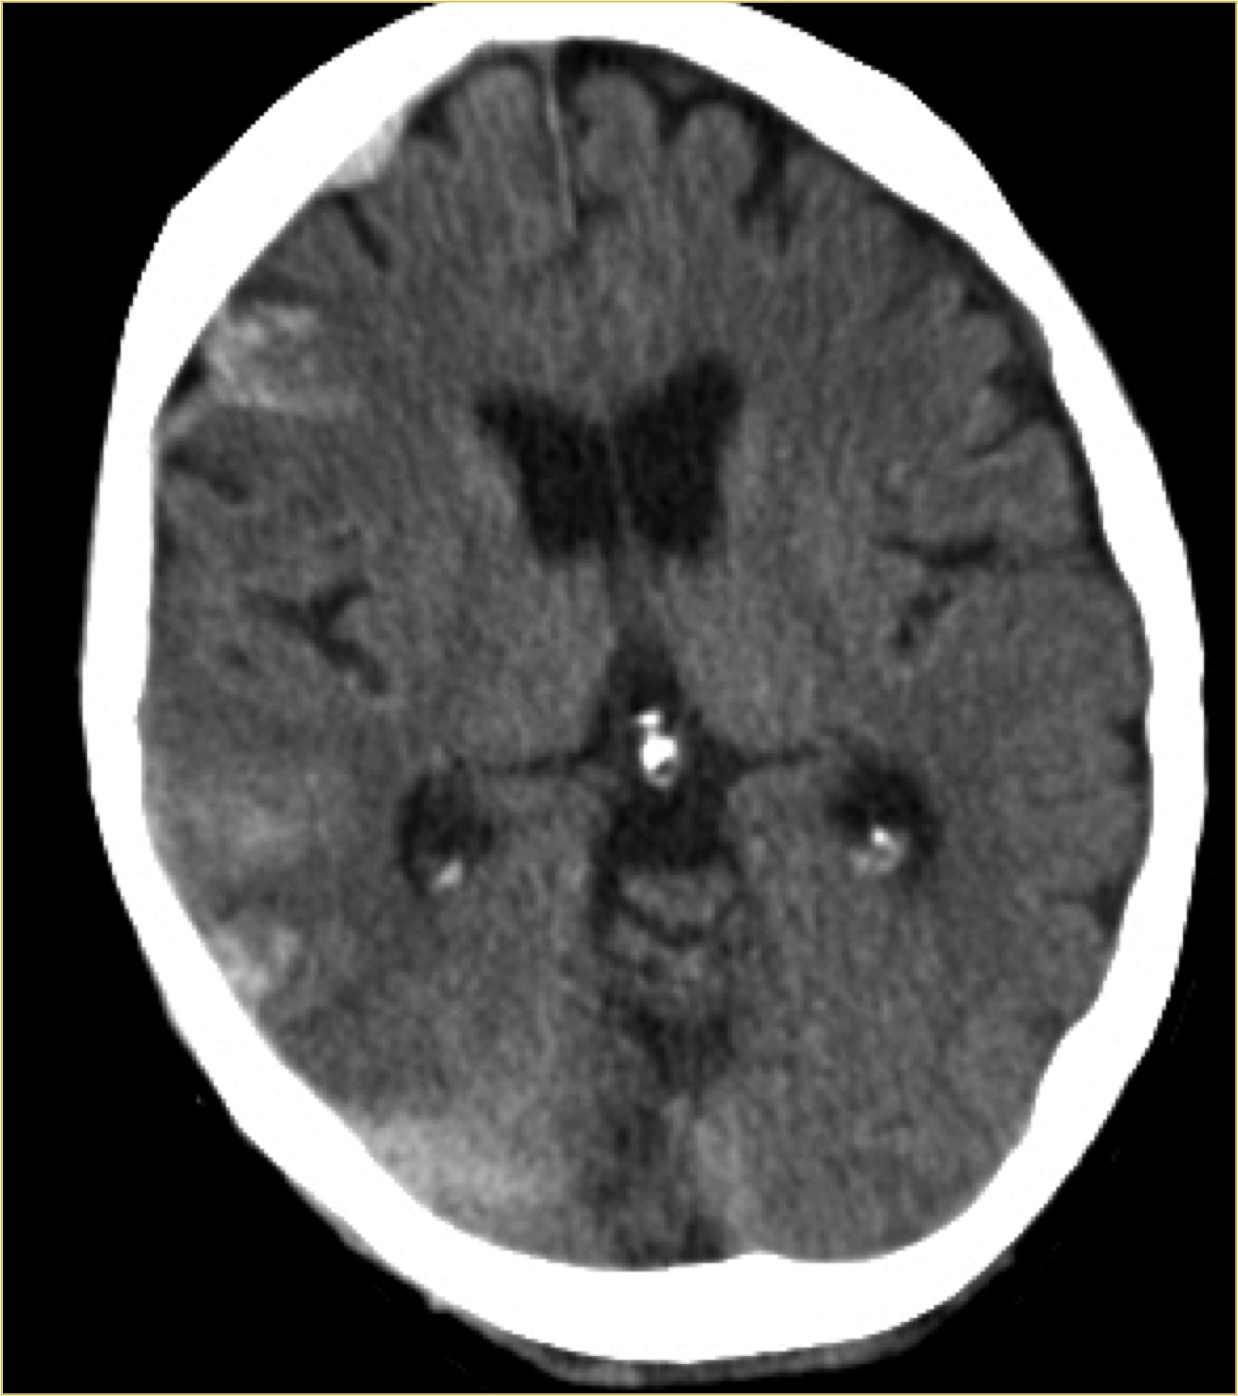

Transtentorial: puede ser unilateral/uncal o bilateral/central.

- Por descenso del contenido supratentorial a través de la tienda del cerebelo.

- Puede ser unilateral o Uncal = descenso del uncus hacia el interior de la cisterna supraselar.

- Dilatación del asta lateral contraletaral

- Dilatación de la cisterna ambiens y prepontina ipsilateral.

- Bilateral o Central = obliteración las cisternas basales

- Hay riesgo de infartos por compresión la ACP y perforantes.

- Pueden producir hemorragias de Duret (mesencéfalo) o de Kreonhan (pedúnculo cerebral contralateral)